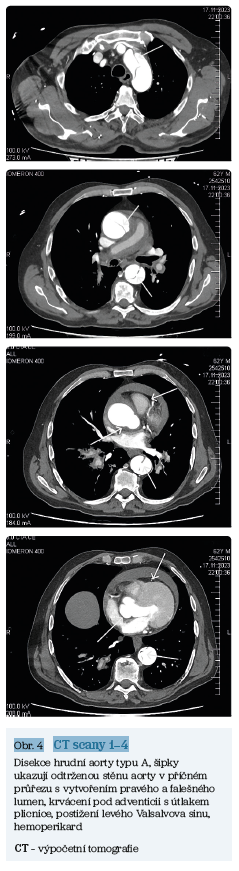

CT scany A–D (obr. 4) zobrazují klasickou disekci hrudní aorty typu A u 62letého pacienta, hypertonika, kuřáka vyšetřeného na Emergency původně pro akutní tepenný uzávěr pravé dolní končetiny.

Spektrum morfologických a histopatologických změn stěny aorty nám objasňuje vznik a vývoj různých typů aortálních lézí (obr. 1, obr. 2).

Výpočetní tomografie (CT) thorakoabdominální aorty v celém jejím rozsahu, s odstupem karotických, brachiálních, viscerálních a iliackých arterií je nejpřesnější zobrazovací metodou. Umožňuje stanovit lokalizaci a rozsah aortálního postižení, včetně malperfúzních syndromů, perikardiálního a pleurálního výpotku, eventuálně dalších patologií, které určují prognózu pacienta. Používáme CT scany aorty v nativním zobrazení a s aplikací kontrastní látky, s EKG synchronizací obrazů.